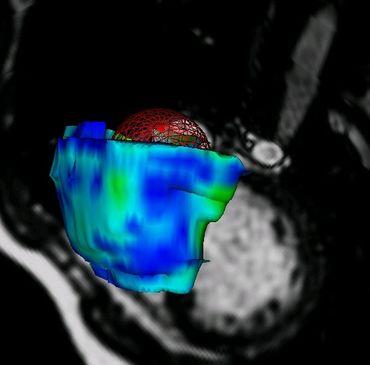

Procesamiento de Imágenes Vectoriales y 4D MRI - Medical Image Analysis (MIA99) (pdf)

DescargarEcocardiografía 3D+T- Transactions on Medical Imaging (TMI02) (pdf)

TODOS LOS CÁLCULOS, IMÁGENES Y ANIMACIONES en esta página y artículos, fueron producidos con PROGRAMAS ESCRITOS POR MI en C / C++ y VTK/TCL/TK

Imagenología Médica del Corazón y Neurociencias

Resonancia Magnética Nuclear ( NMR / MRI )

Ultrasonido / Ecocardiografía 3D ( 3D ECHO )